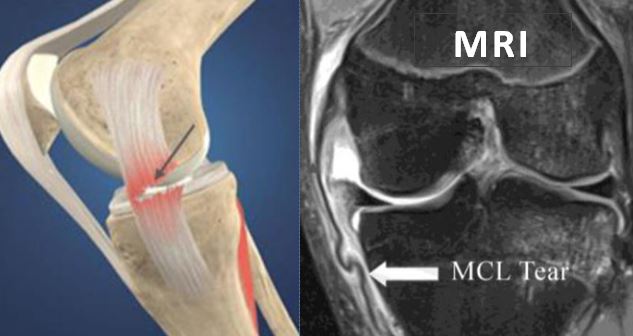

Medial Collateral Ligament or MCL is a band of tissues on the inner aspect of the knee. It runs from the thighbone to about six cms below the knee joint to the shinbone. Sportsmen playing soccer, hockey, and basketball or skiing are more likely to suffer from Medial Collateral Ligament (MCL) Tear. Also MCL tear can result from motor vehicle accidents. MCL is the most important stabilizer of the knee, crucial for normal knee function.

The doctor puts stress on the knee to know the actual ligament which is torn. Once the clinical diagnosis is arrived, an X-Ray is asked for to know the status of the bones of the knee.

MRI scan helps to know the extent of the MCL tear, and the condition of the other ligament structures. It is not uncommon to see associated meniscal injuries in cases of MCL tear.